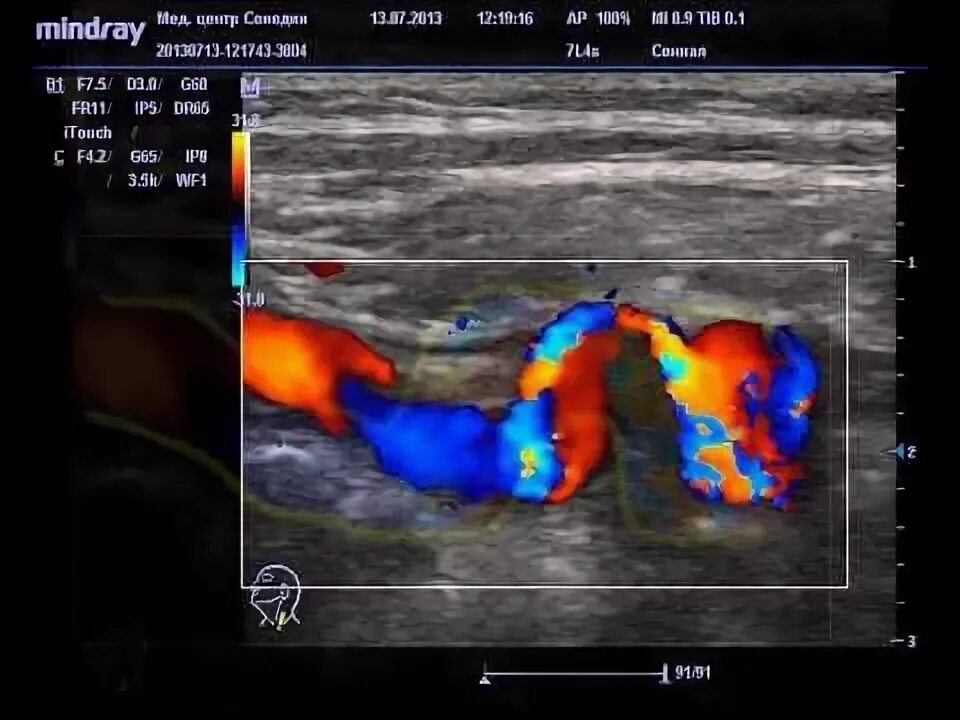

С образная извитость артерий